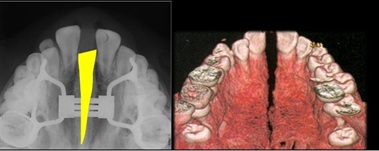

As the name implies, it is a device that acts on the palate by expanding it rapidly and in its most common form it consists of a central screw with 4 arms attached to 2 or 4 bands or to an acrylic resin splint (a bite block) [25]. It acts in a short time not only by distracting the median suture of the maxilla, but also by activating the circummaxillary sutures (scalar, frontonasal and pterygopalatine zygomatico) [26-27]. With its action it directly and indirectly involves the structures connected to the maxillary bone such as the nasal cavities, the pharynx, the pterygoid process of the sphenoid and the mandible. The characteristic of ERP is the application of a high force (up to 10 kg) on the posterior dentoalveolar processes of the maxilla to which it is anchored [28-29]. Initially the dentoalveolar processes undergo a tilting movement (tipping movement of the molars), after which the force transmitted to the maxillary sutures causes a separation of the two halves of the palate along the median palatine suture (Figure 2): the final result is a variation in the width of the jawbone. The opening of the suture is clinically manifested by the appearance of an interincisal diastema, which closes spontaneously in the 2/3 months for skeletal recurrence and traction of the transseptal fibers.

Figure 2: The two halves of the palate along the median palatine suture.